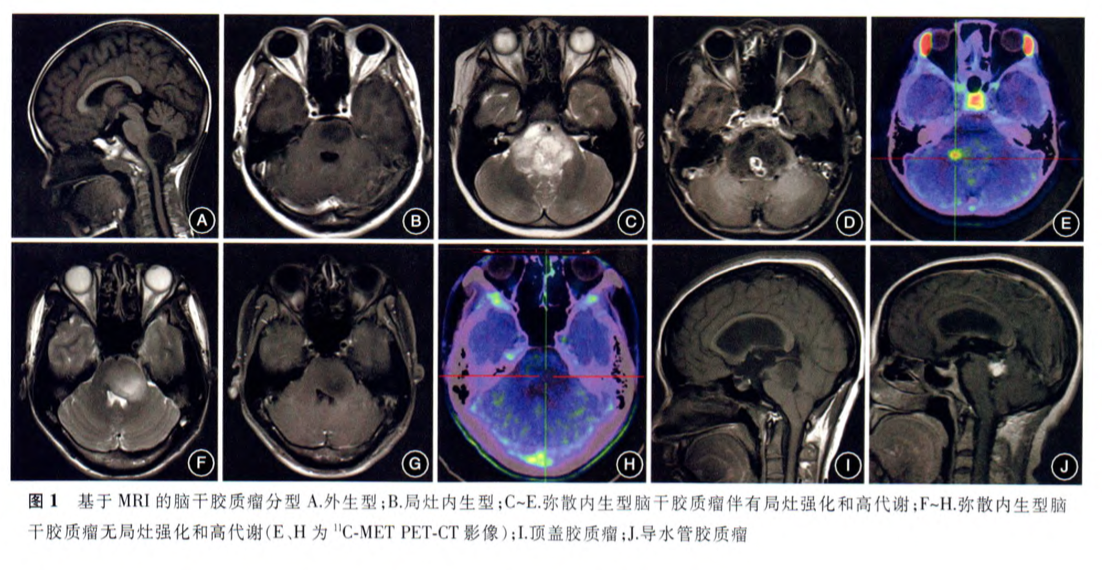

根据MRI肿瘤生长特点将脑干胶质瘤BSG分为3型,外生型BSG、内生型BSG及不同类型的BSG,而弥漫型内因性脑桥胶质瘤 (diffuse intrinsic pontine glioma, DIPG)弥漫性浸润性生长、恶化进展快,属于其中预后较差、治疗难度较大的一种。进来收到很多DIPG的咨询,本文结合较新的临床研究进展,着重介绍DIPG。

影像学MR解析

图:<T2-weighted FLAIR sequence〉整个脑干(延脑、桥脑、中脑)在T2WI上都有信号增强的病灶(黄色箭头)。脑室系统虽被挤压变形,但未出现脑室扩大、水脑的情形(蓝色箭头)。(图1)病灶将脑桥撑大,怀疑往外长出小的外凸物(绿色箭头)。病灶紧邻右椎动脉(红色箭头)。(图2)整个 pons脑桥中充满 hyperintense lesion高信号灶,pons 体积变大,但形状大致不变。基底动脉被肿瘤包围且被往前推(红色箭头),四脑室被挤压,左边尤甚(蓝色箭头),肿瘤扩散至小脑。(图3)中脑中也见到增强的讯号。

注:脑干肿瘤源自于桥脑者,多数是广泛侵犯(diffuse)又高度恶性(high-grade)的。弥漫型内因性桥脑神经细胞瘤典型表现会侵犯临近的中脑和延脑,沿小脑脚长人小脑,往桥脑池(propontine cistern)长出外凸物(外凸物常伴随水脑,外凸物中常见囊状区域),也常包围基底动脉。肿瘤会使桥脑胀大,但不会造成桥脑位置偏移,往延脑侵犯时也不会损害延脑原本的外形(respectthe boundary) 。<Diffusion-weighted sequence〉图2*是DWI的影像,病灶处(空心黄色箭头)在DWI上与原本桥脑组织相比没有表现增强的讯号(注:本图桥脑看不到正常的组织),表示分子运动与原本相较无受限,因此推测此肿瘤的N/C ratio并不大。